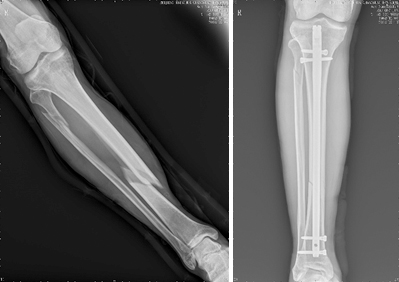

1、复杂关节骨折以及多发创伤的治疗:

随着交通运输、建筑行业的发展,高能量、高暴力的骨折创伤日益多见,特别是发生在关节部位的骨折,若采用传统的石膏固定,则会导致关节部位的僵硬、挛缩。北京清华长庚医院创伤骨科中心诸位医师,通过国际内固定学会(AO-ASIF)相关培训,科学、合理的应用AO原理,对复杂的关节骨折实施手术治疗,可使患者获得早期的功能锻炼,以求得最好的功能恢复。同时创伤骨科中心应用国际最新的微创技术治疗骨折以及多发创伤,进一步减少病人痛苦,加快患者康复,获得良好的效果。

肢体骨折的髓内针微创治疗                  肢体骨折的经皮钢板微创治疗

肢体骨折的经皮钢板微创治疗               复杂关节骨折的手术治疗